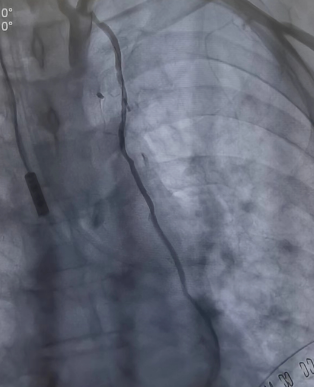

將兩者結合的手術方式就是雜交技術即“一站式微創(chuàng)”手術。手術先在左側胸壁做一個5-7厘米切口,進行左胸廓內(nèi)動脈-左前降支(LIMA-LDA)架橋。接著進行冠脈造影,檢查LIMA-LDA橋血管通暢度。同時在冠脈其他狹窄部位放入冠脈支架。

同期進行冠脈放支架(檢查LIMA橋血管通暢)